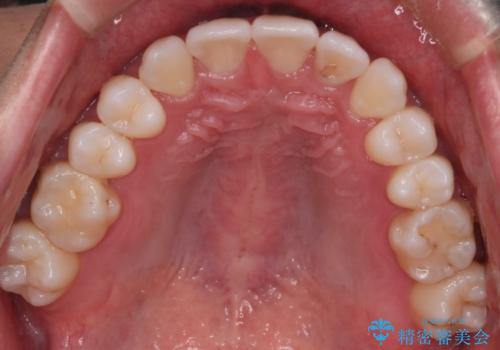

最終的に、見た目も噛み合わせも患者様に満足いただけました。

また矯正後、患者様の希望で

メタルインレーをセラミックインレーにやりかえさせていただき、さらに綺麗に仕上がりました。